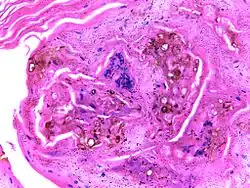

| Micrograph of chromoblastomycosis showing sclerotic bodies | |

The most informative test is to scrape the lesion and add potassium hydroxide (KOH), then examine it under a microscope. (KOH scrapings are commonly used to examine fungal infections.) The pathognomonic finding is observing medlar bodies (also called muriform bodies or sclerotic cells). Scrapings from the lesion can also be cultured to identify the organism involved. Blood tests and imaging studies are not commonly used. On histology, chromoblastomycosis manifests as pigmented yeasts resembling "copper pennies". Special stains, such as periodic acid Schiff and Gömöri methenamine silver, can be used to demonstrate the fungal organisms if needed.